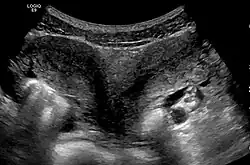

- Class V—Septated uterus (uterine septum or partition).

- The two Müllerian ducts have fused, but the partition between them is still present, splitting the system into two parts. With a complete septum the vagina, cervix and the uterus can be partitioned. Usually the septum affects only the cranial part of the uterus. A uterine septum is the most common uterine malformation and a cause for miscarriages. It is diagnosed by medical image techniques, i.e. ultrasound or an MRI. MRI is considered the preferred modality due to its multiplanar capabilities as well as its ability to evaluate the uterine contour, junctional zone, and other pelvic anatomy. A hysterosalpingogram is not considered as useful due to the inability of the technique to evaluate the exterior contour of the uterus and distinguish between a bicornuate and septate uterus. This condition can be complete or partial

Besides a physical examination, the physician will need imaging techniques to determine the character of the malformation: gynecologic ultrasonography, pelvic MRI, or hysterosalpingography. A hysterosalpingogram is not considered as useful due to the inability of the technique to evaluate the exterior contour of the uterus and distinguish between a bicornuate and septate uterus. In addition, laparoscopy and/or hysteroscopy may be indicated. In some patients the vaginal development may be affected.